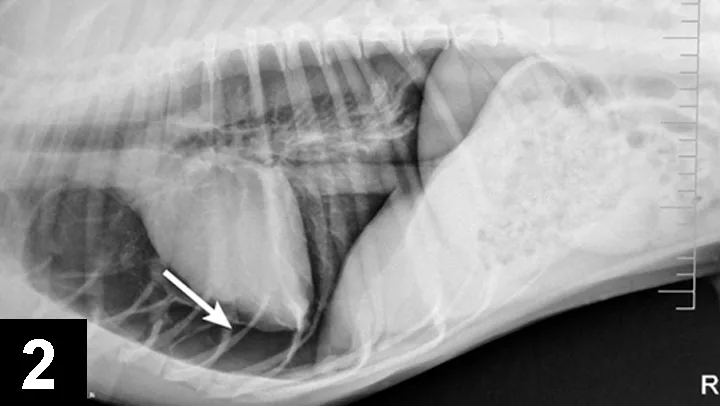

Many illnesses and injuries can impact normal oxygenation and ventilation. Stress, anxiety, and forced activity should be minimized. Pleural space disease (eg, pneumothorax, hemothorax, hydrothorax, pyothorax, chylothorax) can be identified by tachypnea, dull lung sounds with thoracic auscultation, open-mouth breathing, and a dyssynchronous respiratory pattern (ie, opposite motion of the chest and abdomen). Radiographs can identify pleural space disease (Figures 2 and 3) but should not be performed in cases with severe respiratory difficulty. If available, a quick ultrasound of the chest (thoracic-focused assessment with sonography for trauma [TFAST]) can readily identify pleural effusion and can be much less stressful and time consuming than radiography. Supplemental oxygen and thoracocentesis are always indicated.

Figure 2. Right lateral radiograph of a dog with pneumothorax; the arrow indicates the separation of the heart from the sternum.